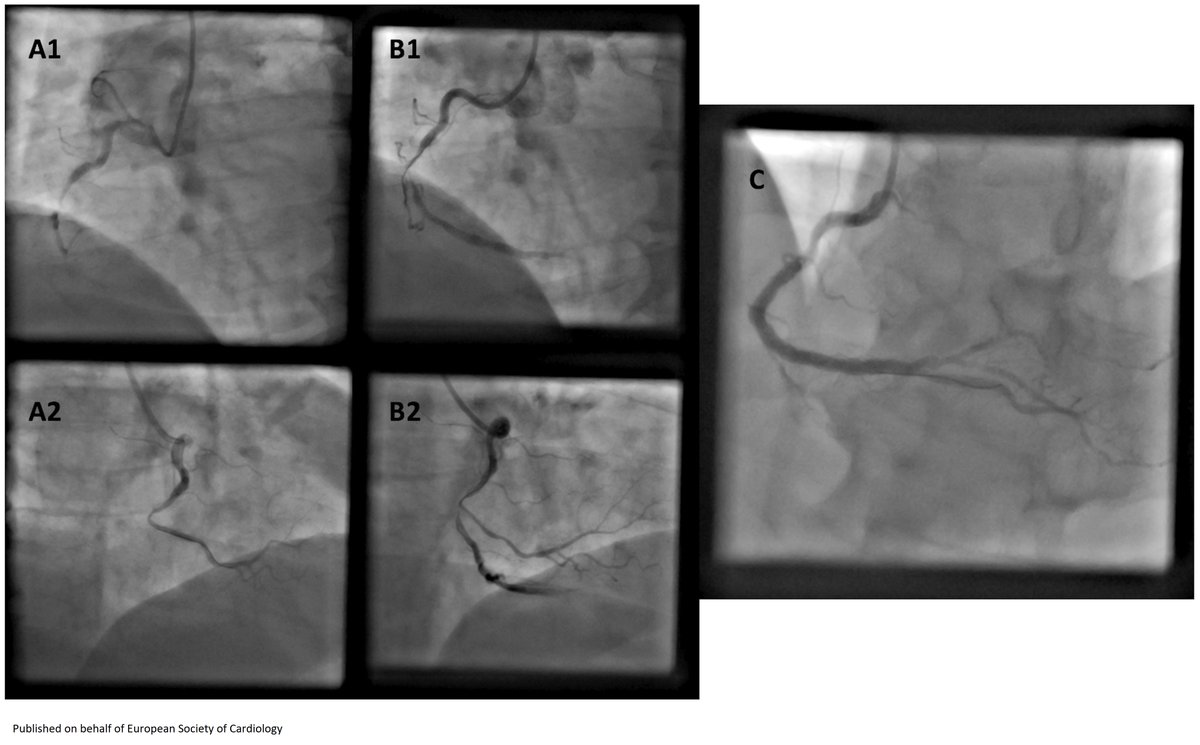

Intracoronary acetylcholine testing without a pacemaker may be one option in the left coronary artery https://t.co/iA9hCI1c0x

#EHJCaseReports @cfcamm @EHJCREiC @TJ_Yeo @aayshacader @FarhanaAra @ANazmiCalik @KardiologieHH